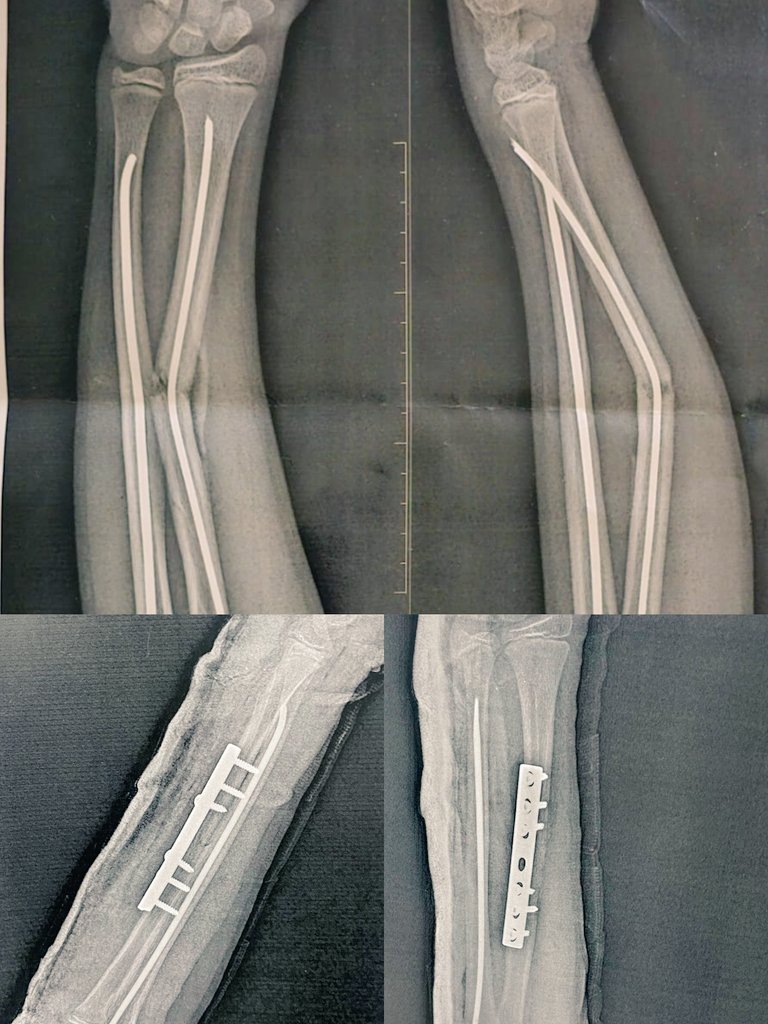

Male pt 13 yrs metal Failure Mid Shaft Radius history of BBFA fixed by ender 1.5 y ago »»» Ender removal and fixation of the fracture by small DCP By thomspon approach ⚔️🥷🤍....

Male pt 13 yrs metal Failure Mid Shaft Radius history of BBFA fixed by ender 1.5 y ago »»»

Ender removal and fixation of the fracture by small DCP

By thomspon approach ⚔️🥷🤍....